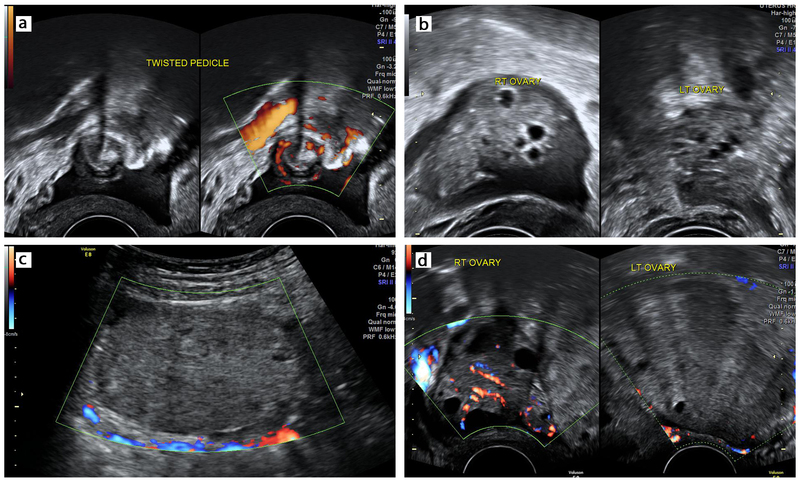

The ultrasound findings of adnexal torsion are summarized in Table 2 and depicted in Figures 1 and 2. An enlarged ovary, hemorrhagic cysts, abnormal position, free fluid and tenderness are commonly seen. The specific findings which can be used in diagnosis are: ovarian stromal edema, whirlpool sign of the twisted pedicle, absent Doppler flow and the follicular ring sign. The contralateral non-torsed ovary provides a convenient control to elicit the sonographic findings.

2

Specific ultrasound findings of ovarian torsion: (a) twisted pedicle with whirlpool sign; (b) follicular ring sign in right ovary and normal antral follicles in left ovary; (c) ovarian stromal edema; (d) absent Doppler flow in torsed left ovary with normal flow in right ovary.

Of the four specific features of torsion, the whirlpool sign is present from the onset in all types of adnexal torsion. As lymphatic and venous flow become compromised, the follicular ring sign is seen as an early feature of ovarian congestion. Ovarian stromal edema with or without peripherally displaced follicles is seen later as ovarian congestion and edema progress. Absent flow is a late feature of torsion when arterial flow is compromised resulting in ischemia and necrosis. This is depicted in Figure 3 and Videoclip 1.